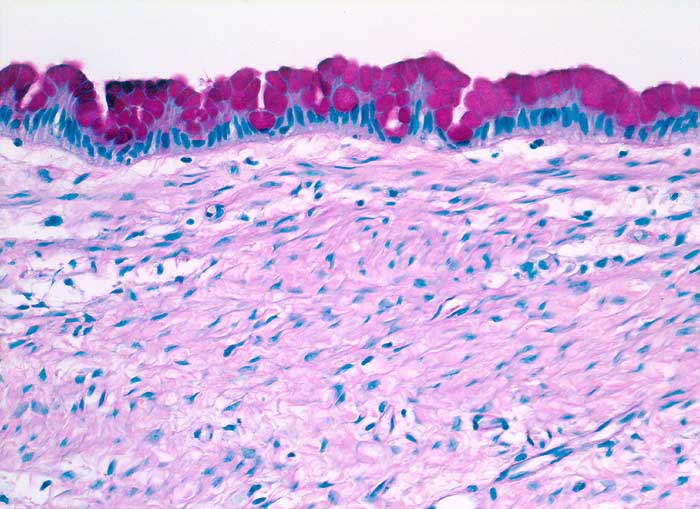

Muzinöses Zystadenom des Ovars

Die gut erkennbaren Zellgrenzen der hohen schlanken Zylinderzellen bilden bei Aufsicht ein Honigwabenmuster. Das Zytoplasma enthält eine grössere oder mehrere kleine apikale Schleimvakuolen, die den Zellkern zur Seite drängen. Das Chromatin ist fein granulär und regelmässig verteilt. Der Nachweis von Schleimbildung schliesst eine funktionelle Zyste aus. Metastasen von schleimbildenden Adenokarzinomen zeigen eine stärkere Kernpolymorphie und bilden keine regelmässigen Verbände.